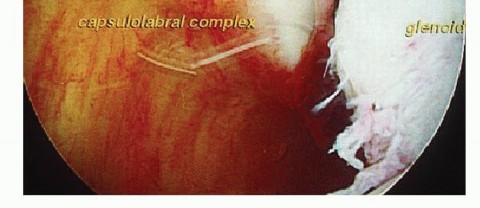

The classic mechanism of injury involves a forceful, catastrophic application of an external rotation and abduction moment to the arm. This leverages the humeral head out of the shallow glenoid concavity, violently loading the anterior capsuloligamentous restraints. This trauma predictably yields the Bankart lesion, the fundamental pathoanatomic hallmark of anterior instability. Originally described by Arthur Sydney Blundell Bankart, this lesion is defined as the avulsion of the anteroinferior labrum and its attached inferior glenohumeral ligament (IGHL) complex from the anterior glenoid rim. Present in up to 90% of traumatic anterior dislocations, the Bankart lesion destroys the essential "bumper" or "chock-block" effect of the labrum and abolishes the critical hammock-like restraint of the IGHL, rendering the joint incompetent.

There is an old orthopedic adage: "If it doesn't bleed, it doesn't heal." The fundamental error in novice Bankart repairs is inadequate tissue mobilization. The labrum and capsule are often scarred medially down the glenoid neck, a classic ALPSA variant. Using an arthroscopic elevator, rasp, or radiofrequency ablation wand, the capsulolabral complex must be aggressively elevated off the anterior glenoid neck.

Image

This release must extend inferiorly past the 6 o'clock position (often requiring a switch of the viewing portal to the anterosuperior portal for adequate visualization) and medially until the red muscle belly of the subscapularis is clearly visualized. The tissue must "float" freely, allowing it to be shifted superiorly and laterally onto the glenoid face without any resting tension.